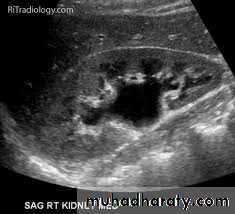

36- Hydronephrosis